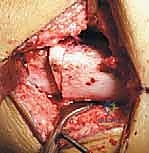

الخطوة الثانية: الشق الجراحي والوصول للعظم

يقوم الدكتور هطيف بعمل شق جراحي دقيق في الجزء الأمامي من الركبة والفخذ السفلي. بفضل مهارته في الجراحة الميكروسكوبية والحفاظ على الأنسجة، يتم إبعاد العضلات والأوتار بلطف بالغ للوصول إلى عظمة الفخذ السفلية (Distal Femur) والوتر الرضفي دون التسبب في تلف الأنسجة الرخوة المحيطة.

الخطوة الثالثة: تقويم عظم الفخذ البعيد (Distal Femoral Extension Osteotomy)

هنا تبرز المهارة الهندسية للجراح. باستخدام مناشير عظمية دقيقة، يقوم الدكتور هطيف بقطع وإزالة قطعة عظمية على شكل إسفين (Wedge) من الجزء الأمامي لعظمة الفخذ السفلية. حجم وزاوية هذا الإسفين يتم حسابها مسبقاً بدقة متناهية بناءً على زاوية التشوه لدى المريض.

بعد إزالة الإسفين، يتم إغلاق الفجوة العظمية، مما يؤدي إلى استقامة عظمة الفخذ والركبة بالكامل. هذا الإجراء يحقق هدفين: يصحح زاوية الانحناء، ويقصر العظمة قليلاً لمنع الشد الزائد على العصب الوركي والشريان المأبضي خلف الركبة.